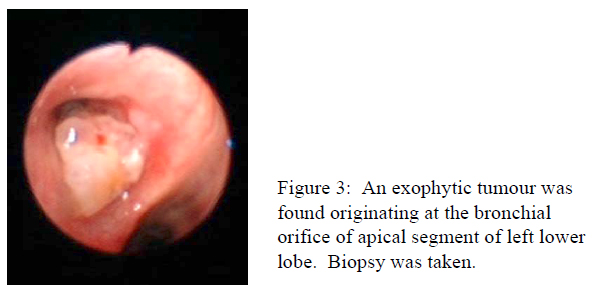

A 61-year-old chronic heavy smoker was incidentally found to have a right lower zone nodule on chest X ray. He had severe chronic obstructive pulmonary disease (COPD) and his FEV1 was 1.32L (38% predicted). A whole body FDG positron emission tomograph and computed tomograph showed hyper-metabolic nodule (2.1×1.6×0.8cm SUV 5.8) at anterior basal segment of right lower lobe and hypermetabolic bilateral hilar lymphadenopathy (right hilar lymph nodes was 1.5×2.6cm and SUV 11.5, left hilar lymph node was 1.0×1.4cm and SUV 8.6). EBUS with TBNA of right hilar lymph node was performed. While the EBUS was approaching the left hilum for hilar lymph node sampling, an endobronchial mass was discovered unexpectedly.

hilar lymph node showed small cell lung carcinoma staining positive for CD 56, thyroid transcription factor-1 (TTF-1) and weakly positive for p63. The endobronchial biopsy from left lower lobe tumour stained positive for p63 and negative for CD 56 and TTF-1, compatible with squamous cell carcinoma. This case illustrate the potential pitfall of missing synchronous lung tumour if the diagnosis is based either on sampling from intrathoracic lymph node or from endobronchial lesion alone. It also demonstrates that adequate tissue can be obtained using EBUS for immunohistochemical staining and differentiation of various cell types of tumour. This case was reported on the journal Lung Cancer.2